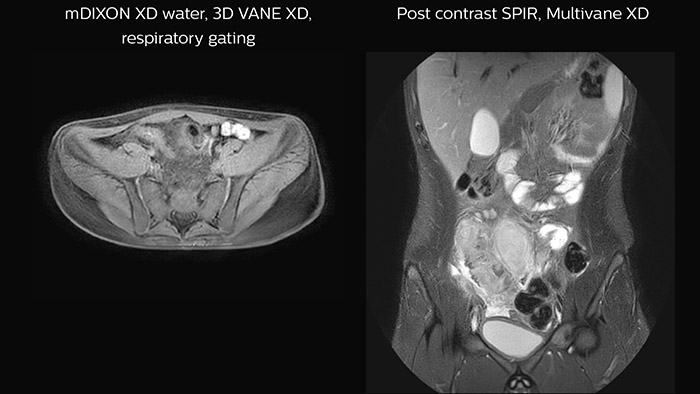

Crohn’s disease in the terminal ileum A large abscess is visible near the terminal ileum, in the middle of the coronal image.

Features that provide remarkable benefits to Dr. Junge include Compressed SENSE, which allows to elevate spatial resolution, signal and scan time. MultiVane XD and 3D VANE XD employ radial k-space sampling and help to mitigate motion artifacts and improve robustness for different contrasts and for all age groups. The mDIXON FFE and mDIXON TSE methods nicely address challenges in fat-free imaging and provide multiple contrast types from one single scan. The achievable large field of view (FOV), high resolution and flexible echo times are certainly a huge benefit in examining children.